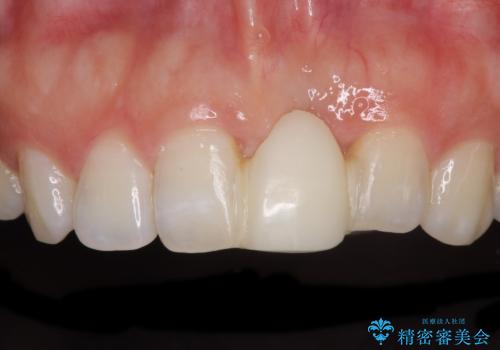

- 接着タイプの前歯のブリッジが不自然であるとのことで来院された患者様です。

欠損部の歯肉が窪んでいるため、歯肉移植により形態を改善し、オールセラミックブリッジにて補綴することとしました。

事前に装着されていた接着タイプのブリッジは、歯の切削量が少ない反面、接着界面から虫歯が進行しやすく、脱落リスクが高くなるというデメリットがあります。